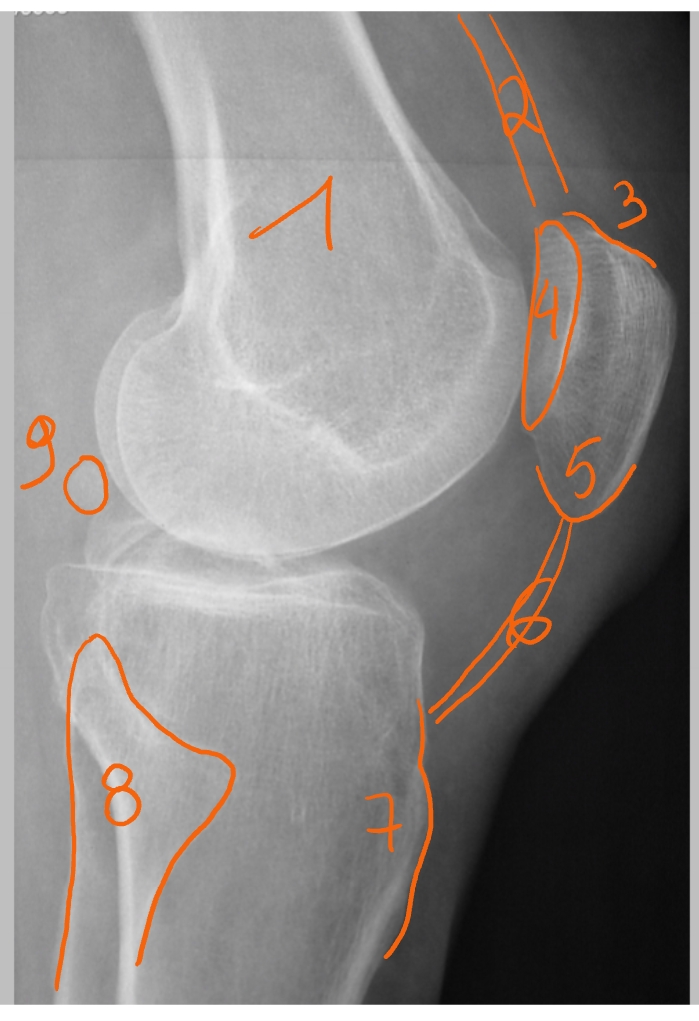

femur

pees van de m. quadriceps

basis patellae

facies articularis van de patella

apex patellae

patellapees/ ligamentum patellae

tuberositas tibiae

fibula

fabella = klein sesambeentje

mediale zijde patellae

laterale zijde patellae

crista

condylus medialis

condylus lateralis

retinaculum = gewrichtsband die patella vasthoudt

= ligamentair

mediale en laterale

→ linker knie (MR): dwarse doorsnede